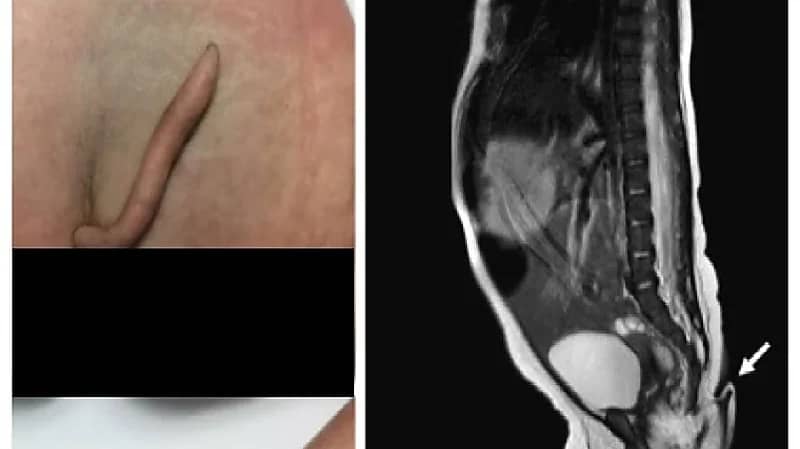

نجح أطباء في إزالة ذيل من فتاة حديثة الولادة، في حالة نادرة للغاية في مستشفى في نويفو ليون، في شمال شرق المكسيك، وكان والداها بصحة جيدة وفي أواخر العشرينات من العمر.

واكتشف الأطباء ذيلا يبلغ طوله 5.7 سم، كان "ناعما" و"مغطى بالجلد والشعر الناعم" وله طرف "مدبب".

وأضافوا إن الطفلة بكت عندما قُرِصَت بإبرة على الذيل. وكانت المولودة تتمتع بصحة جيدة، حيث أظهرت اختبارات الدماغ والقلب والسمع والبول نتائج طبيعية.